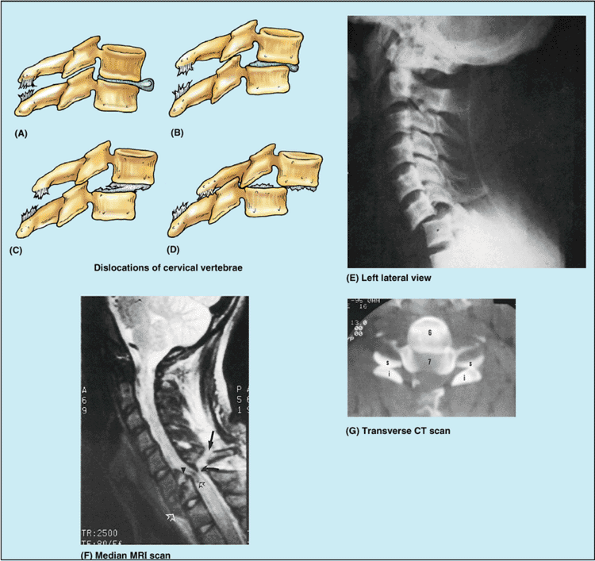

fracture them (Fig. B4.2A–F).

Because of the large vertebral canal in the cervical region, slight

dislocation can occur here without damaging the spinal cord (Fig. B4.2B).

Severe dislocations, or dislocations combined with fractures

(fracture–dislocations) injure the spinal cord. If the dislocation does

not result in “facet jumping” with locking of the displaced articular

processes (Fig. B4.2F & G),

the cervical vertebrae may self-reduce (slip back into place) so that a

radiograph may not indicate that the cord has been injured. MRI,

however, may reveal the resulting soft tissue damage.

![]() |

|

Figure B4.2. Dislocations of cervical vertebrae. Four stages of injury are shown: (A) stage I, flexion sprain; (B) stage II, anterior subluxation with 25% anterior translation; (C) stage III, 50% translation; and (D) stage IV, complete dislocation. E. This lateral view radiograph shows a stage III dislocation with 50% translation. F. This MRI study of a stage IV dislocation with cord injury reveals that the body of C7 is fractured (open white arrowhead). The ligamentum flavum is disrupted (curved black arrow), and the spinous process is avulsed (straight black arrow). G. This transverse CT scan (same as shown in part F)

reveals the reversed position of the articular processes of the C6 and C7 vertebrae owing to “facet jumping.” The flat articular surfaces should be in contact, forming C6–C7 zygapophysial joints. |